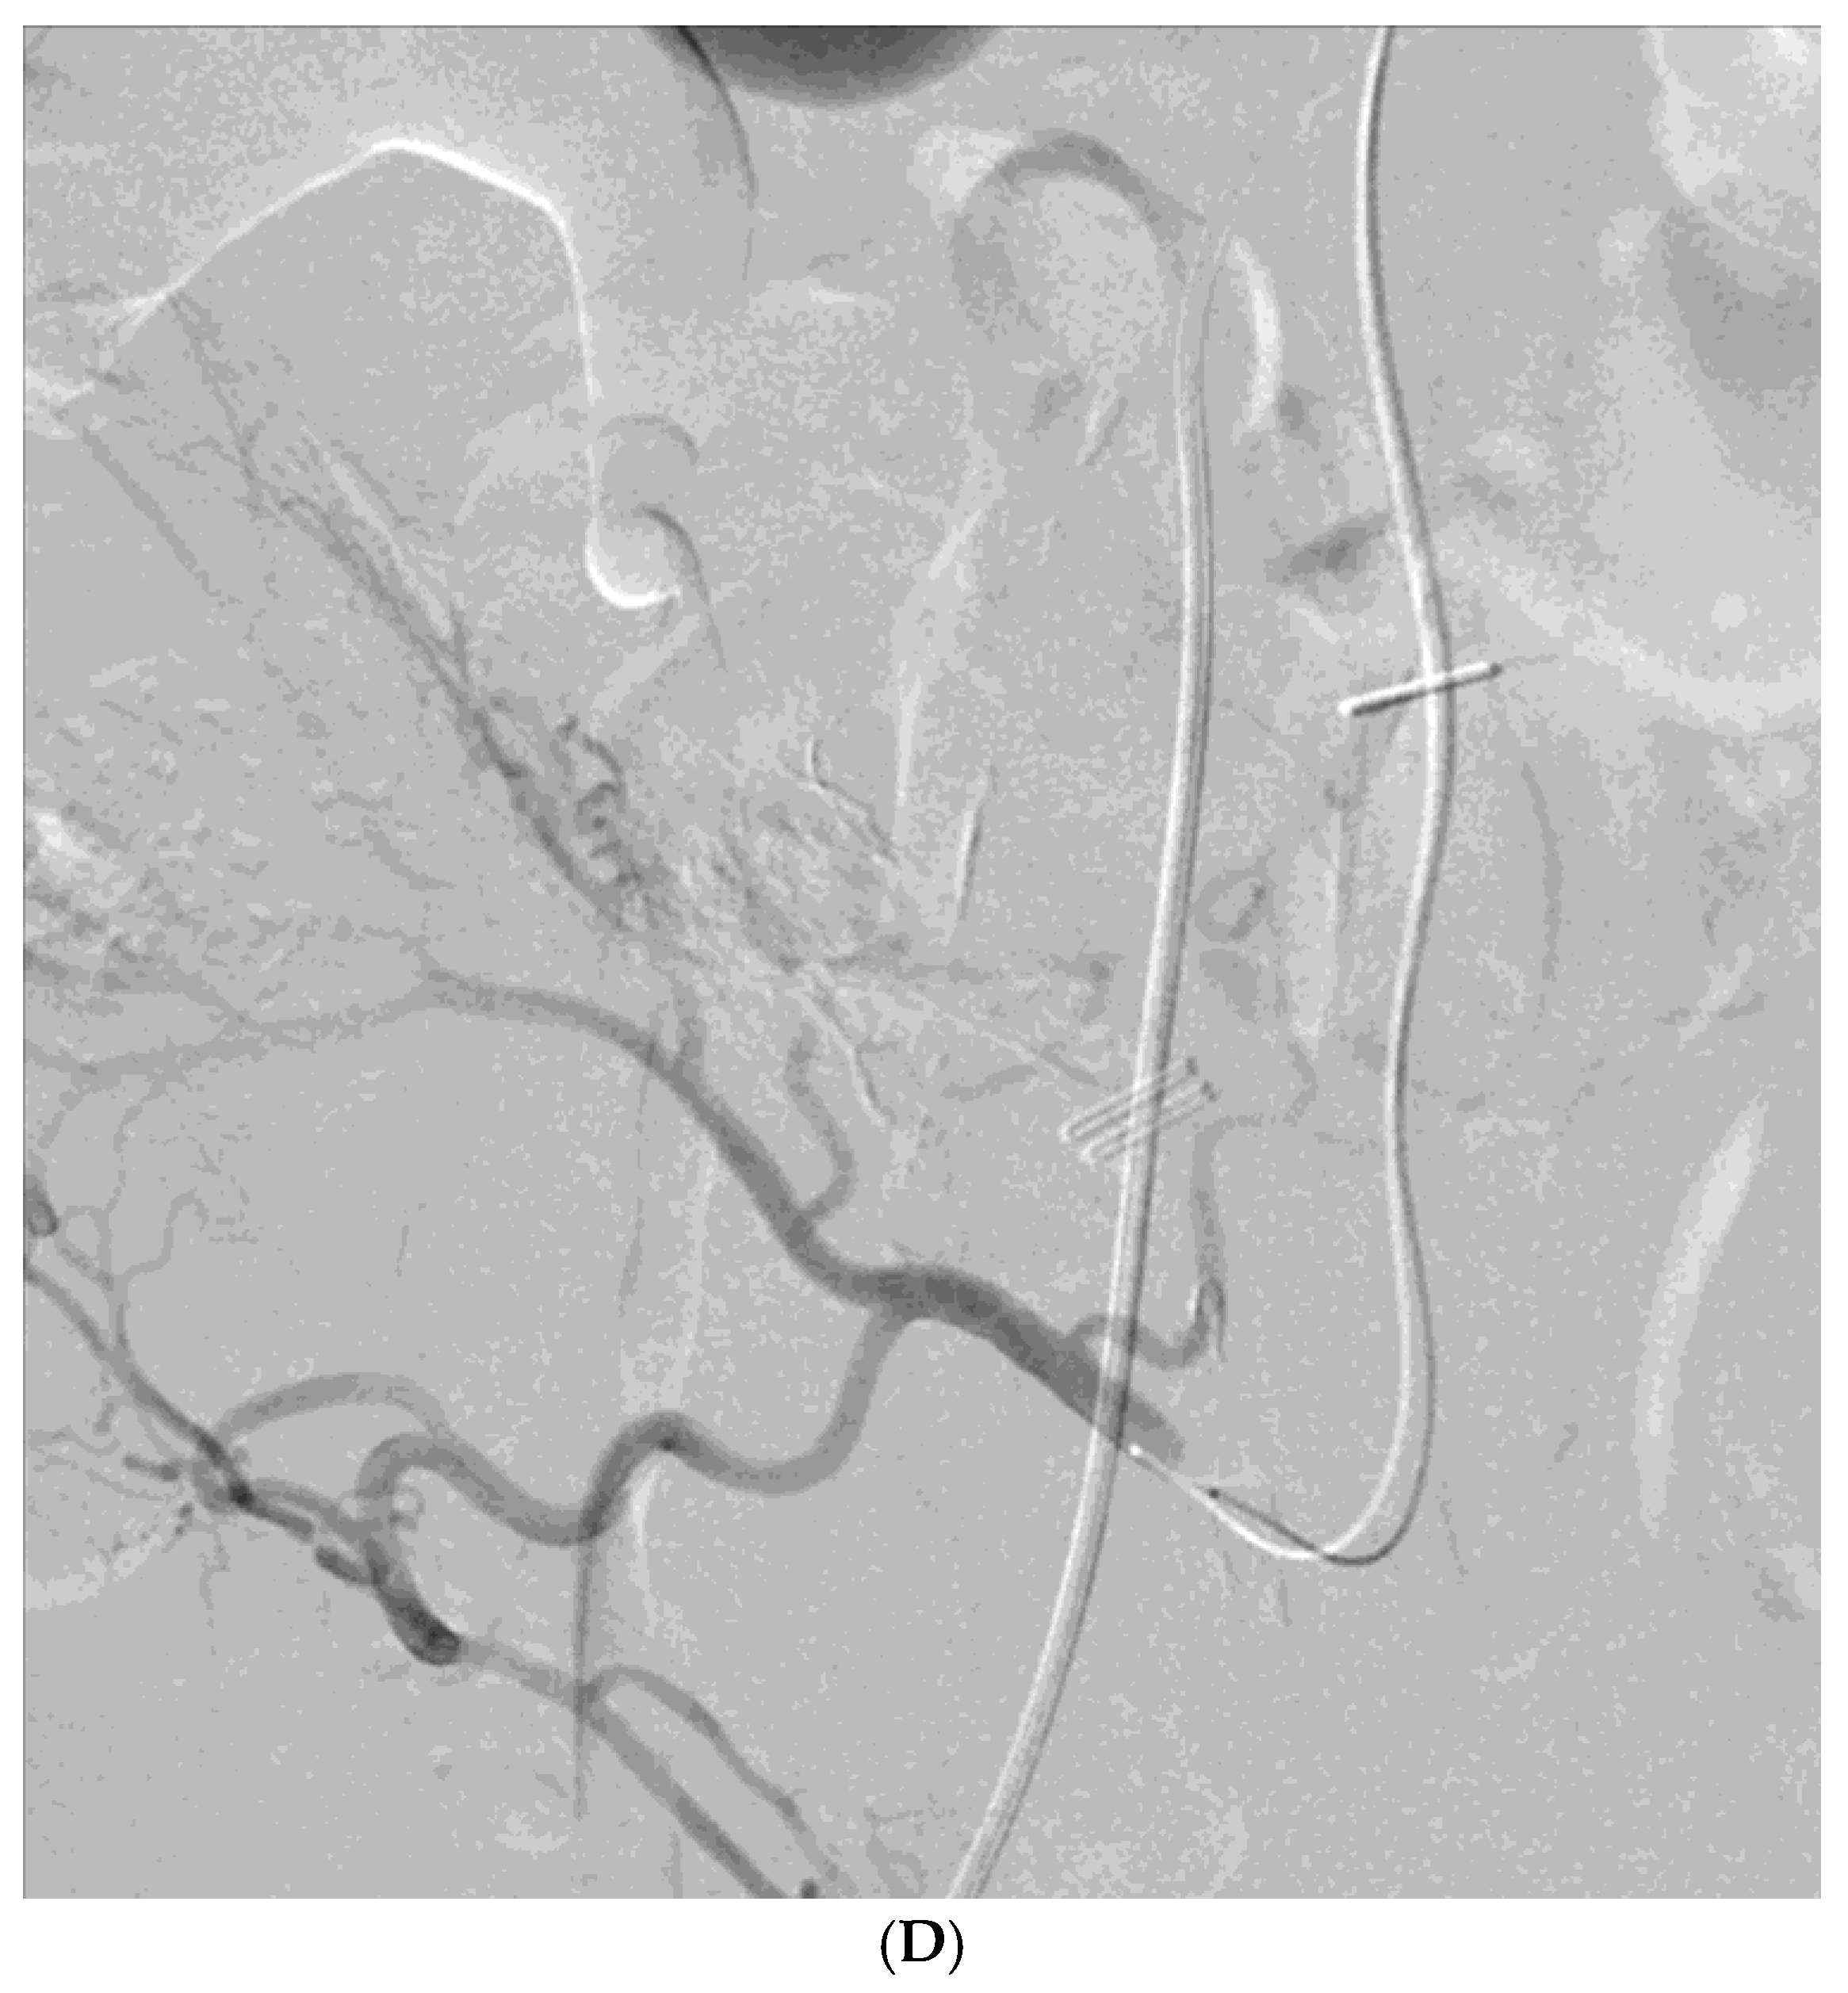

Figure 1. A 78-year-old man presented with hematochezia. (A) Contrast-enhanced axial CT image shows luminal contrast extravasation (arrow) at the ileal loop. (B, C) Selective ileal arteriography shows contrast extravasation (arrows). Due to the distance and tortuosity of the path from the microcatheter tip (arrowheads) to the bleeding focus, superselection was not possible; therefore, embolization was performed using quick-soluble gelatin sponge particles (350–560 µm). (D) Post-embolization arteriography demonstrates that the bleeding focus and the arterial branches leading to it are no longer visible. No further bleeding occurred during the 1-year follow-up.